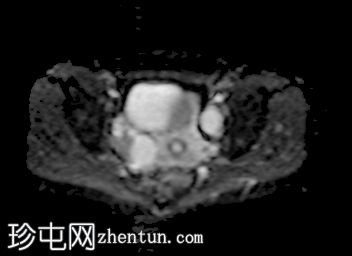

轴向

DWI

此外,所有囊肿均未显示弥散受限或实性成分强化。

本例卵巢囊肿呈中等 T1 信号,类似于肌肉信号,T2 信号高,伴有薄内隔和外周壁强化。但无内部强化或弥散受限。STIR 序列显示与 T2 一致的信号,无任何脂肪成分。该表现提示卵巢出血性囊肿处于早期或消退期。